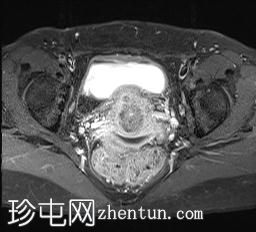

轴位

T1加权像

可见局部晚期浸润性内生型宫颈癌,肿瘤大小为30 x 32 x 48 mm。该肿瘤已侵犯宫颈前唇和后唇的深层间质,以及子宫肌层的下段。

此外,肿瘤还累及宫旁组织。影像学检查发现异常淋巴结肿大,最大短轴直径(SAD)为10 mm,位于髂总血管分叉处和髂内动脉链下方。该淋巴结肿大在弥散加权成像(DWI)上显示水限制,且增强扫描后可见强化。

影像学检查结果提示根据FIGO分期系统,患者为宫颈癌IIIC1期。